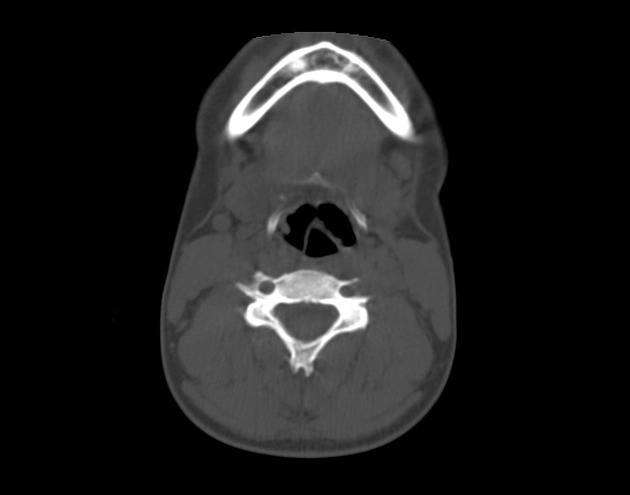

Gãy xương móng

» Thông tin: Nữ giới – 17 tuổi.

» Lâm sàng: Chấn thương vùng cổ.